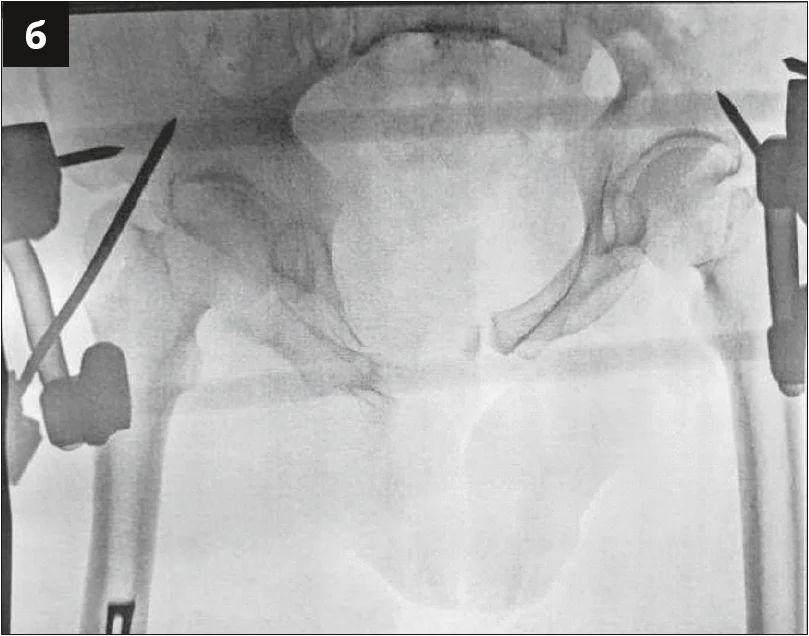

Пораненого негайно доправили до операційної та виконали оперативне втручання за життєвими показаннями, яке включало первинну механічну фіксацію переднього півкільця апаратом зовнішньої фіксації (рис. 2). Згідно з тактикою лікування, розробленою сумісно з хірургічною та анестезіологічною службами, був запроваджений протокол масивної гемотрансфузії, рідинної та медикаментозної підтримки в умовах відділення анестезіології та інтенсивної терапії. Стан постраждалого на кінець першої доби після травми оцінювався як тяжкий, але стабільний. Було прийнято рішення про підготовку до оперативного втручання з остаточної репозиції та механічної фіксації ушкодження таза.

Рис. 2. Рентгенограма таза після виконання його первинної стабілізації апаратом зовнішньої фіксації: а – передньо-задня проєкція; б – проєкція входу в малий таз